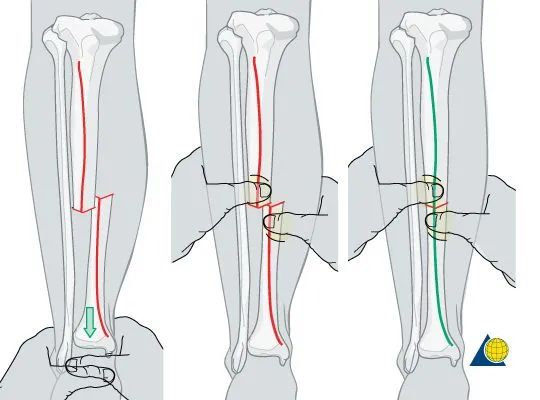

进行纵向的牵引来恢复长度是首要的,

然后同时可以纠正力线和旋转。

手指触摸胫骨前方的骨折断端来进行骨折的复位,

横行的骨折可以通过复位后较好的呆在复位后的位置,

但斜行的比较困难。

横行的复位差不多了后,进行力线和旋转的复位,

以骨折断端胫骨前内侧为模板进行复位,

然后观察整体的力线和旋转。

斜行骨折,前面比较类似,再纠正内外翻的时候需要注意。